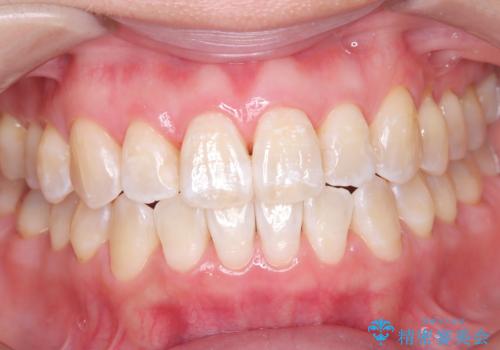

銀座平日限定のオフィスホワイトニングは、痛みが少なく自然な色味希望希望の方にお勧めです

歯の表面に多少の白濁はでていますが、色味のトーンが上がったため満足して頂きました